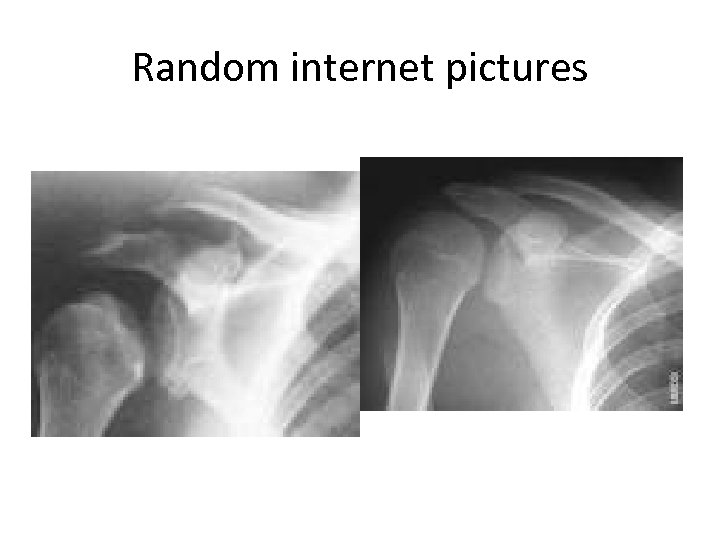

Random internet pictures

Q 1 Name the most likely diagnosis? (1 marks) Q 2 What is the most likely reason for the shoulder injury? (1 mark) Q 3. What two questions would you consider relevant in the medical history in this patient? (1 marks)

Q 1 Likely Posterior shoulder dislocation Q 2 What is the most likely reason for the shoulder injury? (1 mark) • Epileptic seizure while asleep Q 3. What two questions would you consider relevant in the medical history in this patient? (2 marks) • Medication history • Compliance (are you taking your anti-epileptics) • Alcohol history • Seizure history • Previous history of shoulder dislocation